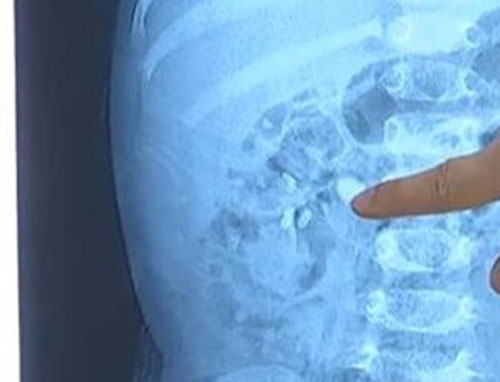

女童出现血尿查出双肾结石,大的结石约2厘米

在广州某医院泌尿外科,通过B超检查发现,双肾多发性结石,左边输尿管上端和下端都有石头塞住,双肾出现了不同程度的肾积水,抽血结果显示肾功能有变化。患儿体内共有9粒结石,其中最大的结石体积达到了2厘米。